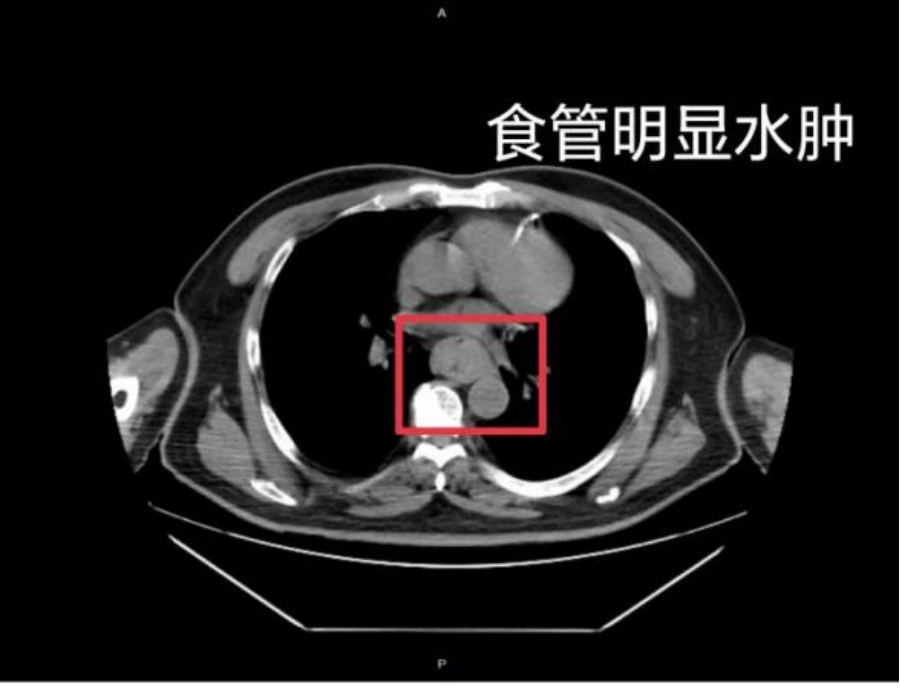

不止一例!去年11月,家住江苏常州的蔡先生在煮好泡面后,未等其冷却便匆忙食用,随后喉咙及食管出现剧烈灼痛。起初他并未重视,但半个小时后,“胸骨后”疼痛依然持续。为了缓解不适,他尝试咽下一口硬米饭,结果发生剧烈呕血,并出现休克症状,家属见状立即将他送往医院。

△图源:常州二院消化内科